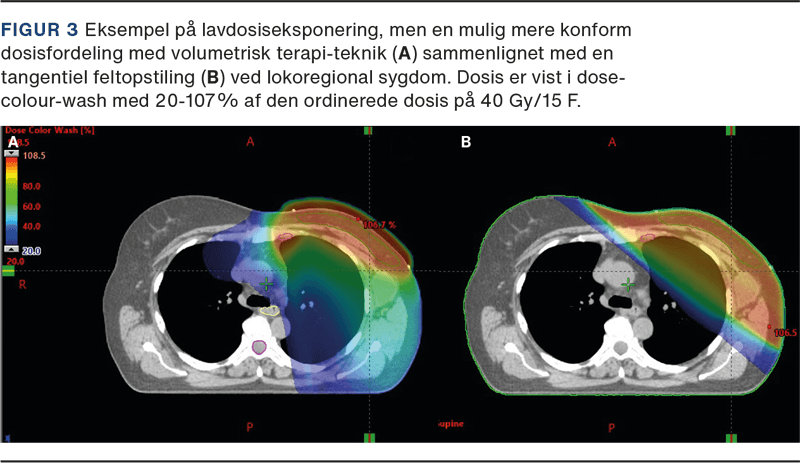

For de få patienter, hvor den planlagte dosis til hjerte og lunger overskrider de anbefalede dosisgrænser, kan brug af moderne planlægning med rotationsteknik være en mulighed. Her omfordeles stråledosis, således at der sikres en mere konform dosisfordeling i højdosisområdet, men til gengæld eksponeres et større volumen af modsatte bryst og lunge, som ellers ikke ville være medbestrålet, for lav dosis (se Figur 3). En anden mulighed er protonbehandling, hvor de anderledes fysiske egenskaber ved protoner potentielt kan forbedre dosisfordelingen. Protonbehandling anses for eksperimentel ved strålebehandling af brystkræft, hvorfor DBCG’s SKAGEN II-studie tilbyder randomisering mellem standardfotonbehandling og protonbehandling til patienter, hvor stråledosis til hjerte og/eller lunger overskrider de anbefalede dosisniveauer.